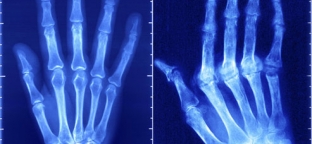

The causes of such a disease as rheumatoid arthritis remain unknown to this day. However, an increase in the number of leukocytes in the blood and an increase in the erythrocyte sedimentation rate indicate that the nature of the process is infectious. Scientists have come close to creating the most effective means to combat this disease.

The disease is suspected to be due to an infection that causes immune system disorders in genetically predisposed individuals.

The disease entails a high risk of disability (70%), occurring quite early. Death from this disease is possible mainly from infectious complications and renal failure. The first manifestation of rheumatoid arthritis can occur after heavy physical exertion, fatigue, shock, as well as during the period of hormonal changes in the body.